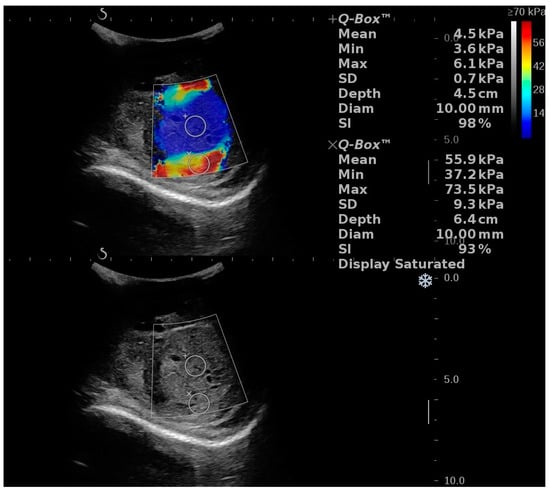

2D SWE